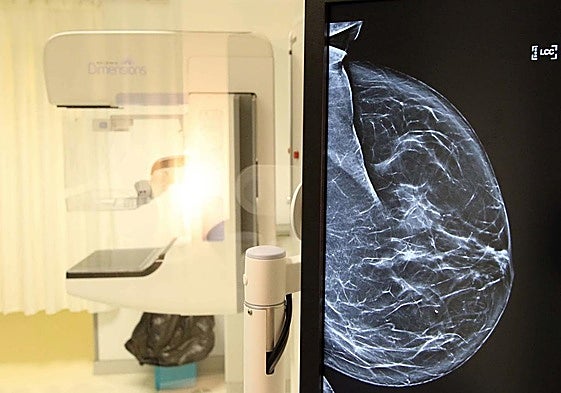

Crece la supervivencia al cáncer de mama en Segovia, pero también la incidencia

El año pasado acabó con una tasa de 150 nuevos casos por cada cien mil habitantes, doce más que un decenio atrás